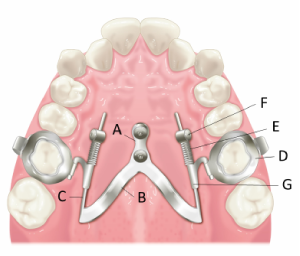

In light of such points, I devised SHU-form with the purpose of ensuring maxillary molar distal movement as intended and improving problems such as lingual discomfort (Figure 1). In the SHU-form, a main part of superstructure connected to the heads of the palatal mini-screws is located in the posterior area of the palate. The guiding part for sliding the maxillary molars mesiodistally is placed to pass near the center of resistance of the maxillary molars from the distal to mesial direction.

Figure1. SHU-form

The SHU-lider device is a mini-screw anchored maxillary molar distalizing device manufactured with the SHU-form design in the palate through the application of CAD/CAM technology. To date, a prefabricated plate or ring have been used most commonly as the abutment for connecting with the heads of the mini-screws. The SHU-lider device features a custom-made superstructure by utilizing CAD/CAM technology composed of a coupling, which is fixed with the head of the anchor screw, a connector, and a guide (Figure 2). The connector extends in a plate shape from the posterior coupling toward the distal palatal portion of the molar. At the plate end of the distal palatal portion of the connector, the guide for sliding the molars mesiodistally is connected so as to pass near the center of resistance of the maxillary molars from the distal to the mesial direction. This guide can be welded with a stainless-steel wire, it is also possible to manufacture a guide by applying CAD/CAM technology.

Figure 2. SHU-lider device.  A: Coupling, B: Connector, C: Guide, D: Molar band, E: Open-coil spring, F: Activation lock, G: Sliding hook

It is necessary to use molar bands, open-coil springs, activation locks, and sliding hooks inserted into the palatal sheaths on the molar bands as a component for directly exerting orthodontic force on the maxillary molars. The distalizing force is delivered by open­coil springs, activated by activation locks, to sliding hooks inserted into lingual sheaths on the molar bands. The molar bands, palatal sheaths, and sliding hooks can also be custom-made by CAD/CAM technology.